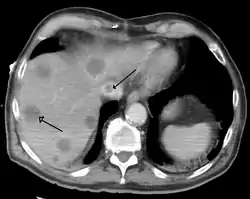

متلازمة بود كياري

متلازمة بود كياري أو بود شياري (بالإنجليزية: budd chiary Syndrome) هي حالة نادرة تصيب 1 من كل مليون من البالغين.[1] تتمثّل بإنسداد الأوردة فوق الكبدية وتتميز بالثلاثي العَرَضي

- التصوير الطبقي المحوري